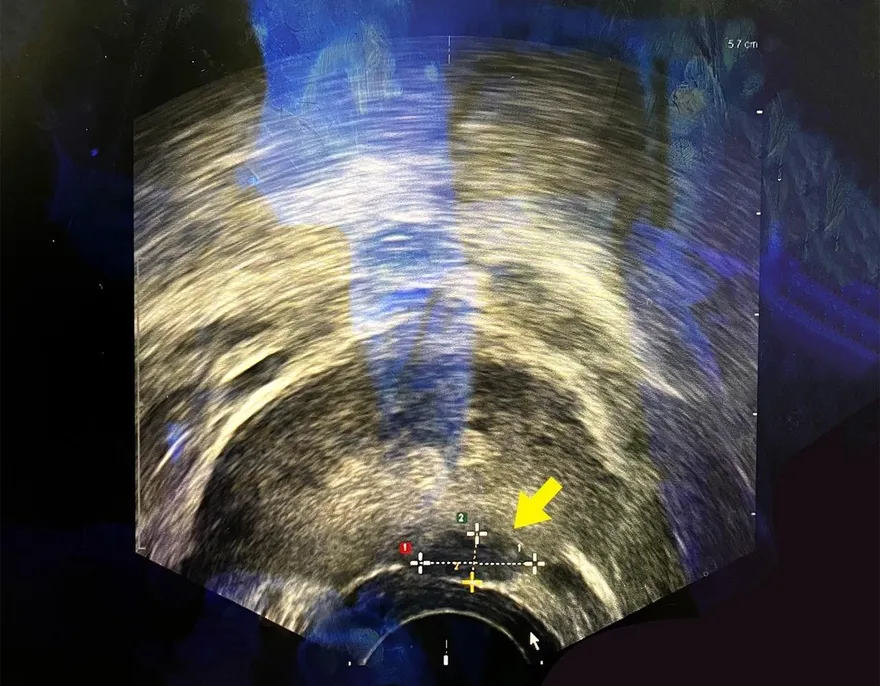

6旬男怕術後失性功能!選「海神刀」消融攝護腺癌零傷口

攝護腺癌

海神刀